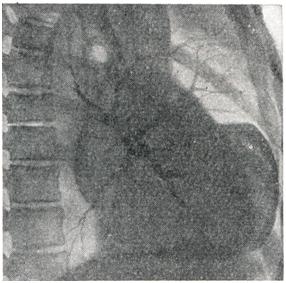

Рентгенодиагностика аневризмы сердца начала развиваться в двадцатых годах 20 в. [Кристиан, Фрик (Н.А. Christian, H.Frick), 1922] и продолжает совершенствоваться, обогащаясь новыми методиками, и. все же распознавание этого заболевания представляет значительные трудности. Для диагностики аневризмы сердца необходима многопроекционная рентгеноскопия с тщательным изучением особенностей сокращений сердца с целью выявления свойственных аневризмам зон акинезии («немых зон») и дискинезии (парадоксальной пульсации). Кроме рентгенограмм в прямой и косых проекциях, рекомендуются рентгенограммы с небольшим поворотом больного (на 20 — 30°) как в правое, так и в левое косое положение. В тех же проекциях производят рентгенокимографию и электрокимографию. Наиболее важным признаком мешковидной аневризмы сердца служит полуовальное выпячивание на контуре левого желудочка (рис. 2 и 3), отграниченное с обеих сторон «зарубками». Для большой аневризмы сердца характерно резкое увеличение поперечника сердечной тени. Левый контур сердца при этом нередко имеет прямоугольные очертания (рис. 4.). Эти грубые морфологические признаки непостоянны и часто отсутствуют при диффузных аневризмах. Поэтому большое значение приобретает симптом волнистости контура, то есть слабо выраженные, иногда едва заметные плоские выпячивания. Роль этих признаков резко возрастает, если соответственно такому выпячиванию наблюдаются и нарушения контрактильных свойств миокарда в виде неподвижности контура или парадоксальной пульсации. Следует учесть, что прослеживание феномена парадоксальной пульсации по заднему контуру левого желудочка во втором косом и боковом положениях может наблюдаться и в норме вследствие систолического преобразования формы сердца. Иногда по контуру левого желудочка видны небольшие углообразные деформации контура (сращения перикарда). В распознавании функциональных признаков аневризмы сердца большое значение имеет рентгеноскопия, но для детального изучения необходима графическая запись движений сердечного контура — рентгенокимография и электрокимография. На рентгенокимограммах отчетливо определяются зоны акинезии, их локализация и протяженность. При сопоставлении рентгенокимограмм аорты и сердца обнаруживаются несвоевременные — парадоксальные (в систоле — кнаружи) смещения контура в области аневризмы сердца, а иногда также признаки резких пассивных смещений истонченной фиброзной стенки аневризмы сердца в виде «оторванных сегментов» сердечной тени или парадоксальной поперечном полосатости сердечной тени (М. А. Иваницкая, 1950). Преимуществом электрокимографии является возможность более точного анализа йарушений контрактильности миокарда: при записи движений контура левого желудочка в области аневризмы сердца определяется подъем кривой во время систолы вместо спуска ее в норме, причем одновременная запись электро- или фонокардиограммы позволяет точно установить время возникновения этого парадоксального движения, продолжительность и амплитуду его по отношению к общей амплитуде кривой. Различают полную парадоксальную пульсацию контуров аневризмы, когда движение в систоле кнаружи занимает всю систолу (это особенно резкие нарушения контрактильности миокарда), и частичную парадоксальную пульсацию, когда это движение занимает лишь часть систолы; при этом зубец как электрокимографической, так и рентгенокимографической кривой приобретает дополнительную вершину. Большое значение для распознавания аневризмы сердца имеет рентгенокимография, обеспечивающая одновременное изучение морфологических и функциональных признаков. Функциональные рентгенологические признаки облегчают диагноз плоских, диффузных аневризм, не дающих выразительном морфологической картины. Для выявления верхушечной аневризмы сердца рекомендуется исследование при глубоком вдохе или с раздуванием желудка. Аневризмы нижней стенки левого желудочка не распознаются при обычном рентгенологическом исследовании. Наиболее точную морфологическую и функциональную характеристику аневризмы сердца в настоящее, время обеспечивает киновентрикулография [Горлин (R. Gorlin), 1967], с помощью которой ныинляются аневризмы любой локализации. Сравнение данных комплексною рентгенологического исследования сердца до и после операции позволяет дать объективную оценку результатам хирургического лечения аневризмы сердца. Использование современных специальных методов исследования позволило повысить частоту прижизненной диагностики аневризмы сердца, что имеет большое практическое значение в связи с успехами хирургического лечения этого заболевания. Аневризма сердца относится к прогностически неблагоприятным осложнениям инфаркта миокарда. Многочисленные отечественные и зарубежные статистики показывают, что спустя 5 лет после инфаркта миокарда, осложненного аневризмой, в живых остаются не более 12% больных. В первые 3 года после инфаркта, осложненного аневризмой, умирают 73%, а через 5 лет — 88% больных, в том числе от сердечной недостаточности — 70% и от тромбоэмболических осложнений — 30%, хотя имеются отдельные указания о продолжительности жизни больных до 10 и более лет. Другими осложнениями, приводящими к смерти больных аневризмой сердца, являются повторные инфаркты и реже — разрывы аневризмы. Поэтому в настоящее, время консервативное лечение следует использовать только для борьбы с осложнениями и как подготовку к операции. Оперативному лечению подлежат: 1) больные с хроническими аневризмами сердца, осложненными сердечной недостаточностью, стенокардией, аритмией, неподдающиеся консервативной терапии; 2) больные с аневризмой сердца, осложненными тромбозом мешка или его прогрессивным увеличением, грозящим разрывом. Только у некотоорых больных с небольшой неосложненной диффузной или мешковидной аневризмой сердца при стабильном состоянии операцию можно отложить при условии диспансерного наблюдения до изменения клинической картины.Резекция мешковидных аневризм сердца должна производиться не ранее чем через 3—4 месяца после перенесенного инфаркта, то есть когда образуется прочная рубцовая ткань, предупреждающая несостоятельность швов по линии иссечения аневризматического мешка. Исключением являются быстро увеличивающиеся аневризма сердца Операция не должна производиться больным с большой диффузной аневризмой сердца при плохой функции оставшейся части желудочка. Относительным противопоказанием к хирургическому лечению аневризмы сердца является возраст больных — старше 65 лет. В связи с тяжелым состоянием больных и сложностью операций вмешательства при аневризме сердца носили до середины 50-х годов 20 в. случайный характер. В 1931 г. Зауэрбрух (Е. F. Sauerbruch) во время операции на грудной клетке по ошибке вскрыл аневризму правого желудочка, принятую им за опухоль средостения, ушил ее у основания и иссек. В 1942 г. Бек (С. S. Beck) укрепил свободным куском широкой фасции бедра стенку постинфарктной аневризмы левого желудочка, диагностированной дооперации. С 1944 г. при хирургическом лечении хронической аневризмы сердца применяется ряд вмешательств: 1) укрепление истонченной стенки аневризмы различными аутотрансплантатами: грудной мышцей [Д'Аллен (С D. Allen), 1956], большим сальником (В. И. Казанский, 1964), кожным лоскутом [Ниднер (F. F. Niedner), 1955] и др.; 2) погружение аневризмы швами (Б. В. Петровский, Ф. Г. Углов, А. А. Вишневский, 1954 — 1957); 3) погружение аневризмы швами с помощью межреберной мышцы на ножке [Шпачек (В. Spacek), 1954]; 4) резекция аневризмы закрытым способом с использованием игольчатого зажима [Бейли (С. P. Bailey), 1954]; 5) резекция аневризмы на открытом сердце в условиях искусственного кровообращения [Кули, Каткарт, Лиллихей (D. A. Cooley, R. Т. Gathcart, С. W. Lillehei), 1958; Б. В. Петровский]; 6) различные варианты диафрагмопластики — укрепление стенки сердца лоскутом диафрагмы (Б. В. Петровский, 1957). Операция укрепления стенки аневризмы различными тканями применяется в настояшее, время только при диффузной аневризме. При мешковидной аневризме она недостаточна, так как не устраняет парадоксальной пульсации и угрозы разрыва аневризмы. Операция погружения аневризмы сердца швами может применяться лишь при небольших мешковидных аневризмах желудочка или предсердия, случайно выявленных на операции, проводимой по поводу сдавливающего перикардита или ревматических пороков сердца; при аневризмах, осложненных тромбозом, ее нельзя применять из-за опасности эмболии. Прикрытие и погружение аневризмы сердца с помощью межреберной мышцы не нашло широкого применения: ликвидируя парадоксальную пульсацию, это вмешательство не улучшает питания сердечной мышцы. Как показал опыт торакопластики по Абражанову, используемые для пластических целей мышцы всегда рубцово перерождаются; помимо этого, возможна эмболия за счет пристеночных тромбов. Резекции аневризматического мешка закрытым способом относятся к радикальным вмешательствам. Этот метод разработал Бейли, который в 1954 г. выполнил подобную операцию, пережав основание анев¬ризмы специальными клеммами. В дальнейшем пережатие основания аневризмы для предотвращения эмболии он производил только после ее рассечения и удаления пристеночных тромбов. Особое внимание уделяется вымыванию струей крови тромботических масс, что независимо от Бейли предложил Б. В. Петровский для удаления тромбов из ушка и предсердия при операциях по поводу митрального стеноза и аневризмы сердца. Преимущество этого метода состоит в том, что для его выполнения не требуется сложной аппаратуры, он прост и эффективен, а использование вымывания тромбов в какой-то мере служит профилактикой тромбоэмболии. И все же резекция аневризмы сердца закрытым способом, несмотря на меры предосторожности, связана с опасностью возникновения артериальной тромбоэмболии. Этот метод может применяться при резекции небольших мешковидных аневризм, особенно в случаях, когда отсутствуют пристеночные тромбы. Резекция аневризмы сердца открытым способом в условиях искусственного кровообращения нашла широкое распространение во всем мире. Эта операция с успехом была выполнена независимо друг от друга Кули, Каткартом и Лиллихеем в 1958 г. Ее преимущество состоит в том, что можно произвести тщательное удаление тромботических масс, аккуратно иссечь аневризматический мешок, провести ревизию папиллярных мышц, митрального клапана и межжелудочковой перегородки. Большие мешковидные и грибовидные аневризмы следует удалять только этим способом. В мировой литературе описано свыше 500 операций, выполненных при аневризме сердца [Фавалоро (R. Favaloro) — 130, Лиллихей — 126, Кули — 80, Б. В. Петровский — 186, Геберер (G. Heberer) — 6, Бьерк (V. О. Bjork) — 5 и др.]. В СССР первая успешная операция выполнена Б. В. Петровским, им же разработаны (1957) следующие виды операций: 1) пластика диафрагмальным лоскутом на ножке при диффузной аневризме сердца; 2) прошивание основания аневризмы шелковыми швами или танталовыми скобками с помощью аппарата УКЛ-60 при небольших мешковидных аневризмах без тромбоза; 3) резекция аневризмы с удалением тромботических масс из полости желудочка закрытым способом с последующей диафрагмо-пластикой линии шва при мешковидных аневризмах с тромбозом. Диафрагмо-пластика способствует реваскуляризации миокарда путем прорастания сосудов из диафрагмального лоскута в миокард, поскольку такой лоскут на ножке имеет хорошее кровоснабжение и иннервацию. Близкое расположение сердца и диафрагмы, интимные связи их кровоснабжения и иннервации дают основание с успехом использовать диафрагму для пластики стенки сердца. Как показали экспериментальные исследования, этот лоскут очень редко атрофируется, уже через 3—5 месяцев происходит прорастание сосудов диафрагмы в миокард. В клинике с помощью коронарографии доказано наличие густой сети анастомозов между сосудами диафрагмы и сердца через 8 лет после диафрагмопластики (рис. 5).